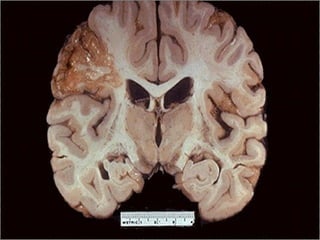

Liquefactive Necrosis

• Usually due to enzymatic dissolution of

necrotic cells (usually due to release of

proteolytic enzymes from neutrophils)

• Most often seen in CNS and in

abscesses

Liquefactive necrosis -- gross

Liquefactive necrosis of brain

Liquefactive Necrosis • Usuallydue to enzymatic dissolution of necrotic cells (usually due to release of proteolytic enzymes from neutrophils) • Most often seen in CNS and in abscesses